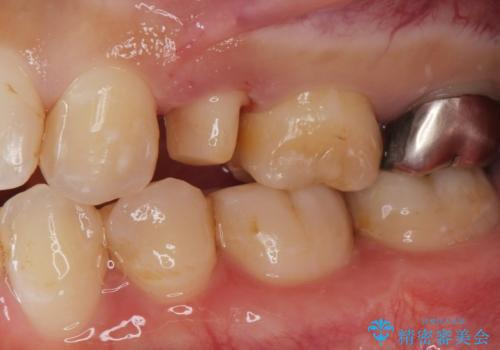

- 他院で被せた保険の白い被せ物(樹脂)をセラミックの被せ物に変えたいとの事で来院。

被せ物を外し、虫歯がないことを確認してセラミックの被せ物(ジルコニアクラウン)の治療を行いました。

白くて適合の良い被せ物が入りました。

セラミックは劣化することがなく虫歯の再発のリスクが低くなります。